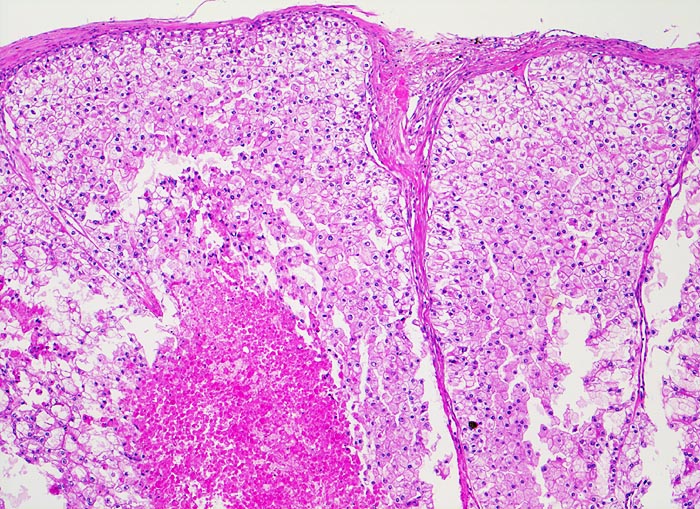

PathoPic – image database / PathoPic ID 4889 - hellzelliges Nierenzellkarzinom

hellzelliges Nierenzellkarzinom

Das Karzinom bildet breite Trabekel aus planzenzellähnlichen Zellen mit reichlich klarem oder helleosinophilem Zytoplasma und deutlichen Zellgrenzen. Ausgedehnte Tumornekrose.

Der typische mikroskopische Aspekt hat dem hellzelligen (= klarzelligen) Nierenzellkarzinom seinen Namen verliehen. Das helle Zytopla kommt durch eine Akkumulation von Phospholipiden, Neutralfetten und Glykogen zustande.